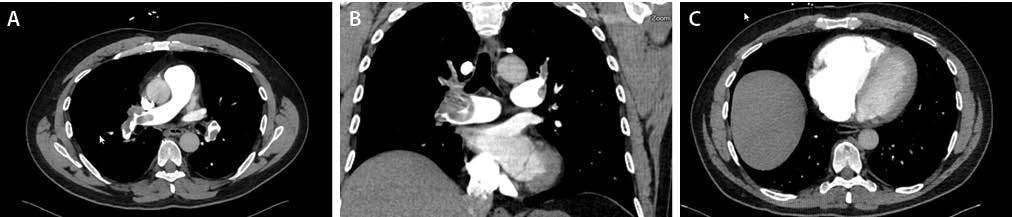

CT pulmonary angiography (CTPA) demonstrated large, multilobar, occlusive (Figure 1A) and near-occlusive emboli (Figure 1B), most prominently in the right lower lobe, with RV dilation (RV/LV [right ventricular/left ventricular] ratio, 1.79) (Figure 1C) and reflux of contrast into the inferior vena cava. Duplex ultrasound confirmed acute DVT in the right popliteal, posterior tibial, and peroneal veins.

Figure 1. Pretreatment CTA demonstrating extensive bilateral PE and signs of RV pressure overload. Axial CTPA showing large, centrally located thrombi involving the right main PA with extension into the lobar and segmental branches of the right lower lobe (A). Coronal reformatted CT images confirming extensive thrombus burden in the right PA system, predominantly involving the lower lobe vasculature, with reduced distal perfusion (B). Axial cardiac CT image demonstrating marked RV dilation with septal bowing consistent with elevated RV systolic pressure; the calculated RV/LV ratio was 1.7, indicating significant right heart strain (C).